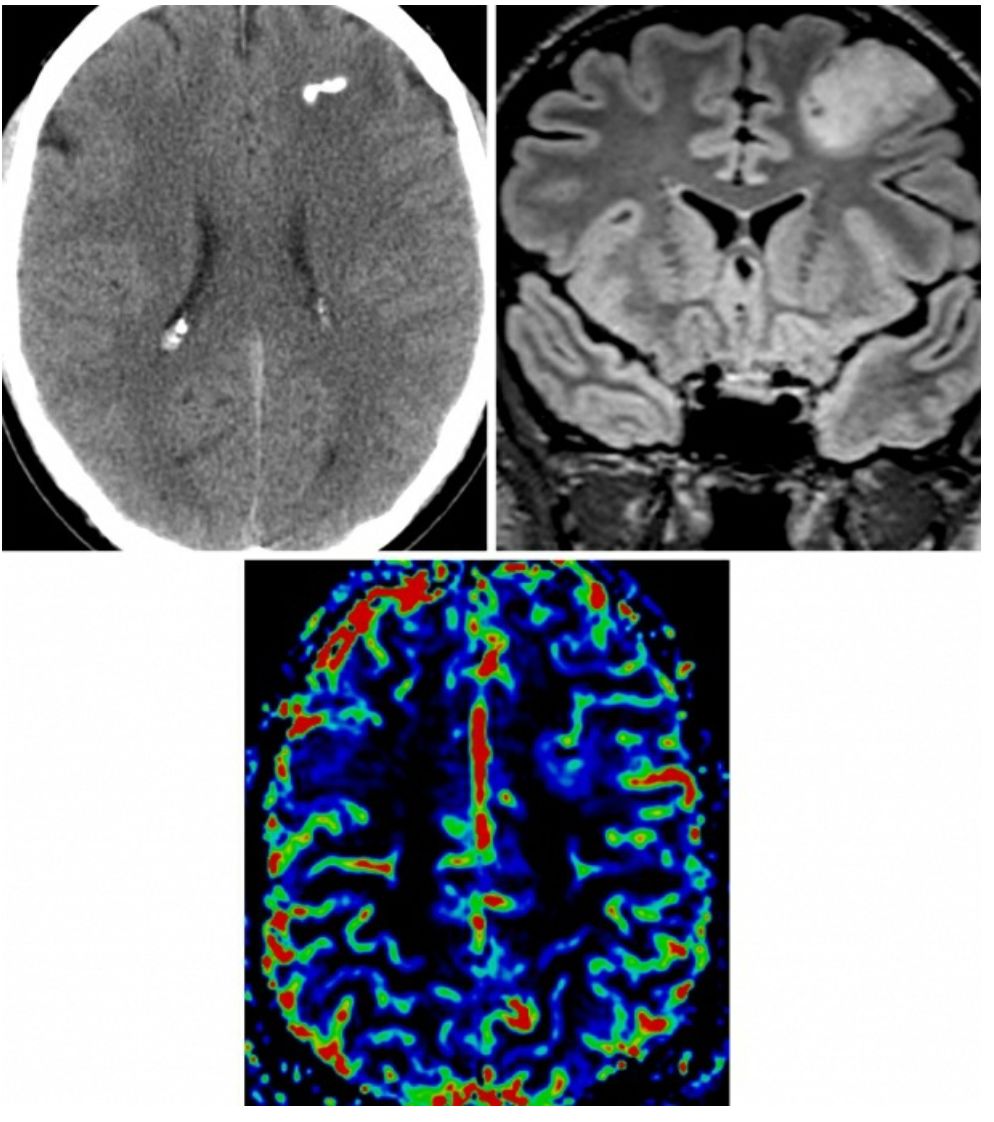

图1. 少突胶质细胞瘤在CT上的特征性改变为肿瘤内部的多发钙化(左上图);在冠状位FLAIR上,肿瘤典型的表现为均匀局限性浸润生长,累积周围的皮层及白质(右上图);在脑血容量灌注图像上,少突胶质细胞瘤表现为轻微低灌注,出现“鸡笼”样血管的病理特征(下图)。

CT

(1)发生于幕上的累及皮质及皮质下白质的等低密度团块影

(2)如果有出血或钙化则表现为局灶性高密度影

(3)CT增强表现为多变的强化效应

(6)MR波谱成像/MR灌注成像:胆碱升高,NAA下降,脂质及乳酸峰缺失(不同于间变性少突胶质细胞瘤);具有相对脑血容量(RCBV)升高的独特特征,但是由于出现“鸡笼”样血管的病理特征,RCBV分级较低